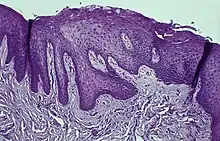

Histology

Immunohistochemical staining with FXIIIa [9] antibody disclosed a population of reactive spindle- or stellate-shaped cells[10] in 11 of 15 cases, located in connective tissue papillae and in a few cases also distributed throughout the lesion. The FXIIIa-stained cells appeared together with the frequently observed stellate, "young" occasionally multinucleated fibroblastic cells observed in more than 50% of patients aged 10–69 years. It is likely that FXIIIA-expressing "mucosal dendrocytes" are pathologically involved in some way.[11][12][13]